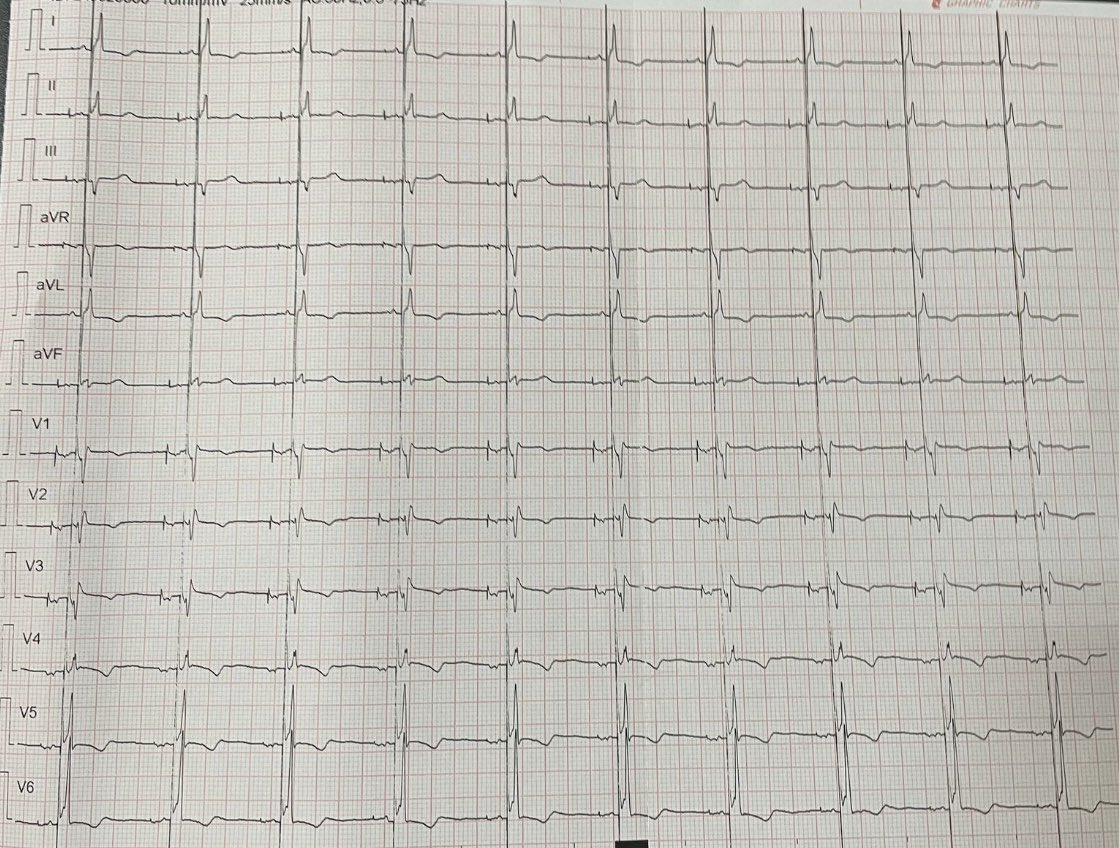

Nice LBBP at Argerich Hospital. @Saidbull @chadid_ok @clabadet